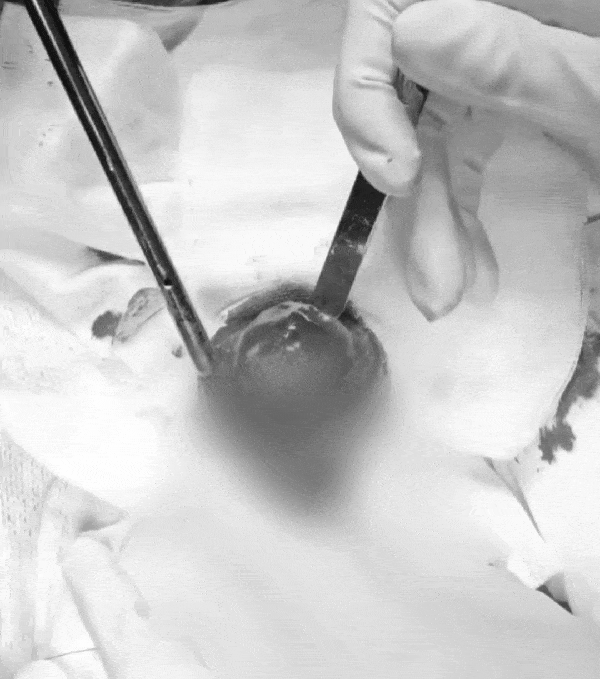

본문 이미지 - 방광 결석 수술 제거 장면(광주 스카이동물메디컬센터 제공) ⓒ 뉴스1

방광 결석 수술 제거 장면(광주 스카이동물메디컬센터 제공) ⓒ 뉴스1